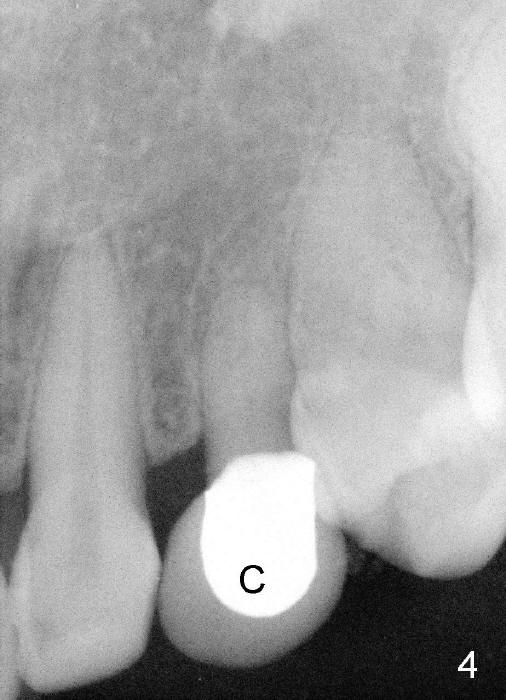

The upper left deciduous canine of a lady in her early forties looks functional 9 and 5 years ago (Fig.1,2). She wanted to close the diastema mesial to the deciduous tooth (Fig.2 *). The tooth was prepared for a provisional (Fig.3 P) and definitive restoration (Fig.4 C). The tooth becomes mobile 4 years post cementation (Fig.5).